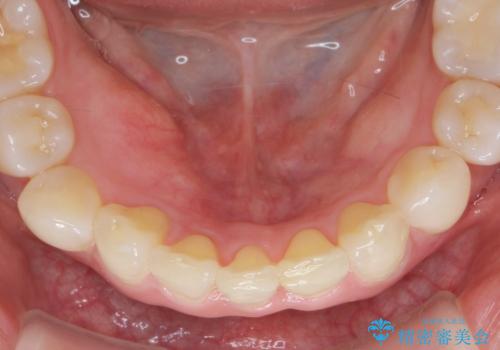

インビザラインで行う前歯のみの部分矯正

- 長年気になっていた前歯の歯並びを改善したいと、矯正治療を希望され思い切って来院されました。

費用と期間を相談し、「気になっているのは前歯だけ。」とのことでしたので前歯のがたつきのみをインビザラインで改善する矯正治療の計画を立てます。

しっかりとマウスピースの装用時間を守っていただき、非常にスムーズに治療を終了することができました。